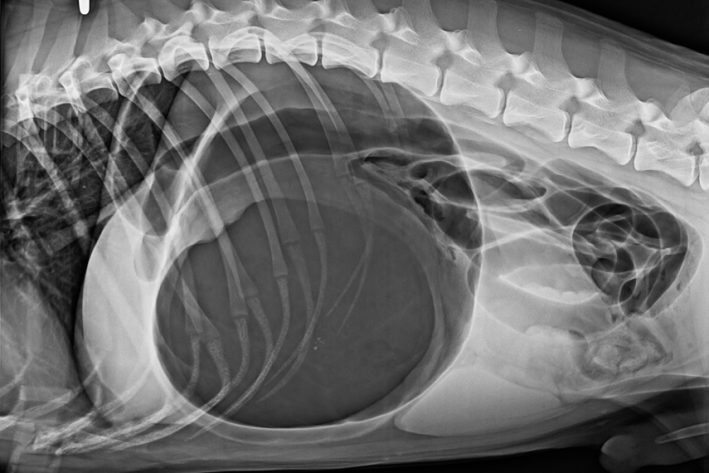

Röntgenaufnahmen sind notwendig, um eine Drehung des Magens von einer reinen Aufgasung zu unterschieden. Das Röntgen zeigt klassischerweise ein seitenverkehrtes „C“ bzw eine „Doppelblase“.

Am Röntgenbild sieht man die typische

Am Röntgenbild sieht man die typische "Zipfelmütze" der Magendrehung